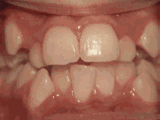

深覆盖,咬牙时,上牙差不多完全把下牙挡住了,黄飞鸿的弟子牙擦苏就是这类,经过矫正后的牙齿是这样的~